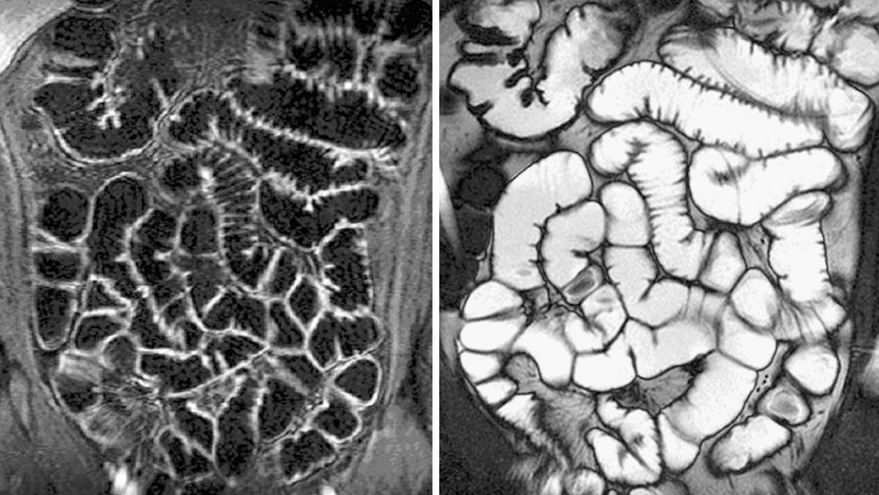

Петли кишечника переплетены и образуют сложный рисунок на экране томографа.